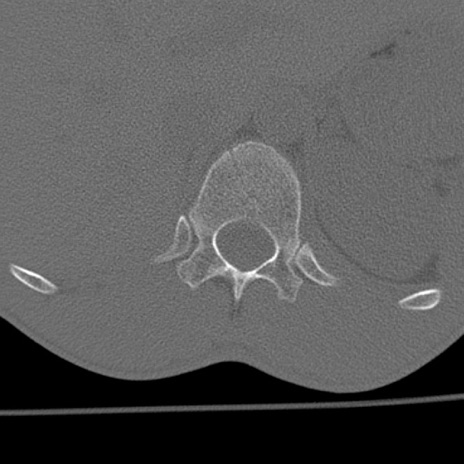

症例3 腰椎CT(横断像)

腰椎CT